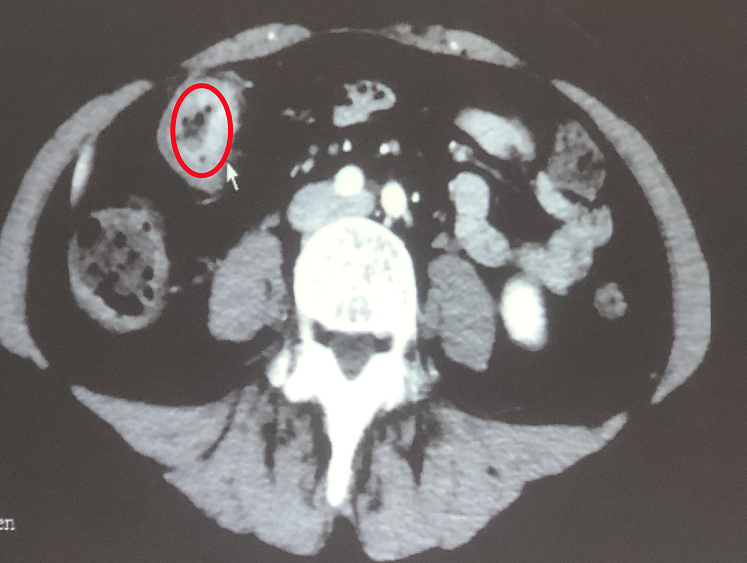

【治疗前影像显示:肠道内有肿瘤(红圈内)】